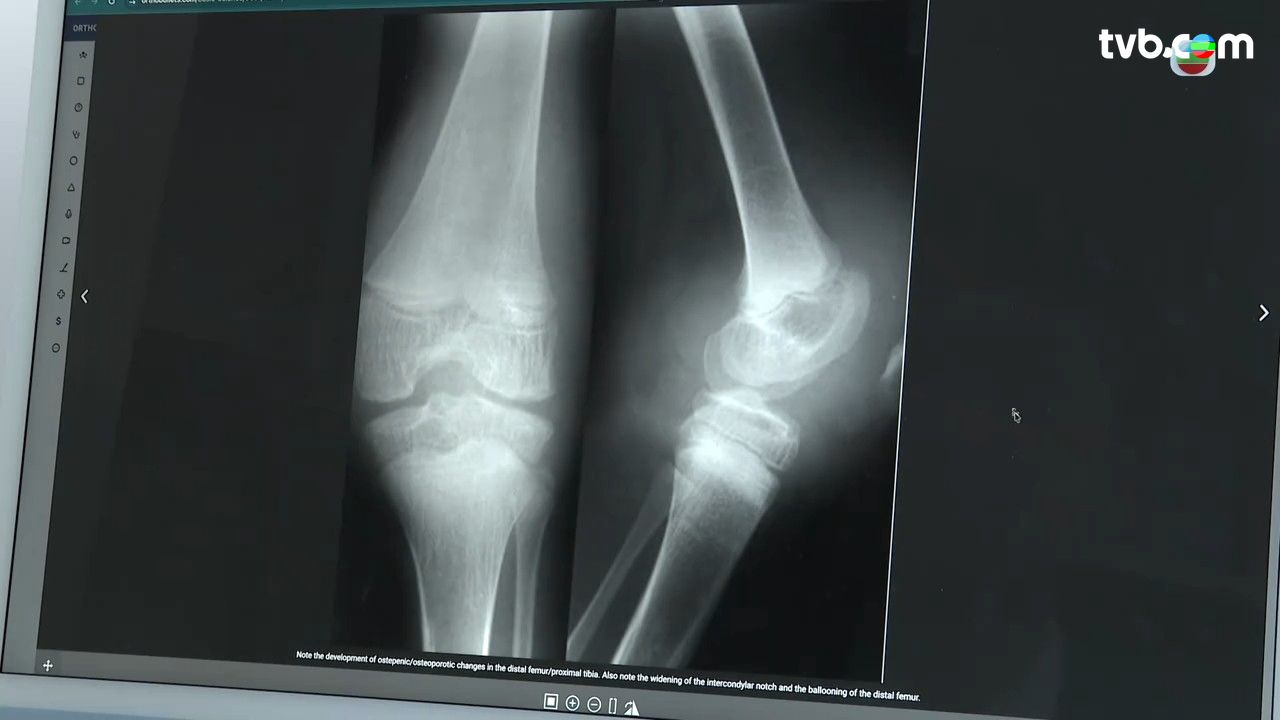

血友病患者需要小心自己患上血友關節病,因為患者常會出現靶關節(Target Joint),即因長期、反覆出血而受損的特定關節。這會導致慢性關節滑膜炎、關節軟骨受損、活動受限等併發症,最後形成永久性關節病變。

為及早發現問題,醫生建議定期進行超聲波檢查。超聲波能評估滑膜與軟骨狀況,透過國際評分機制監察關節變化,比僅靠「疼痛感」判斷更準確。